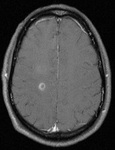

TC de crânio sem contraste de um paciente com encefalite por HSV: mostra hipodensidades sutis envolvendo a região insular esquerda. Algum turvamento das margens cinzas-brancas e apagamento dos sulcos na região temporal esquerda são detectáveis

Do acervo pessoal de Catalina C. Ionita, MD; usado com permissão